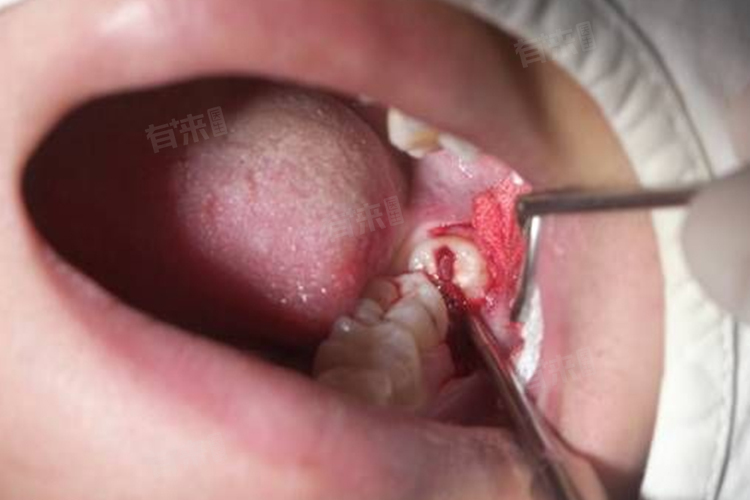

1、创口压迫止血:拔智齿后,医生会在创口处放置棉球,患者需咬紧棉球30-40分钟。这能通过压迫创口,促进血液凝固,形成血凝块,有效止血。若过早取出棉球,创口可能再次出血,影响愈合。在咬紧棉球过程中,尽量减少说话和吞咽动作,防止棉球移位。

5、观察创口情况:密切关注拔牙创口,若创口有少量渗血,属正常现象。但如果出血较多,吐出的唾液中持续有大量鲜血,或血凝块脱落,应及时就医,留意创口是否有红肿、疼痛加剧、发热等症状,若出现异常,可能是感染迹象,需尽快复诊。